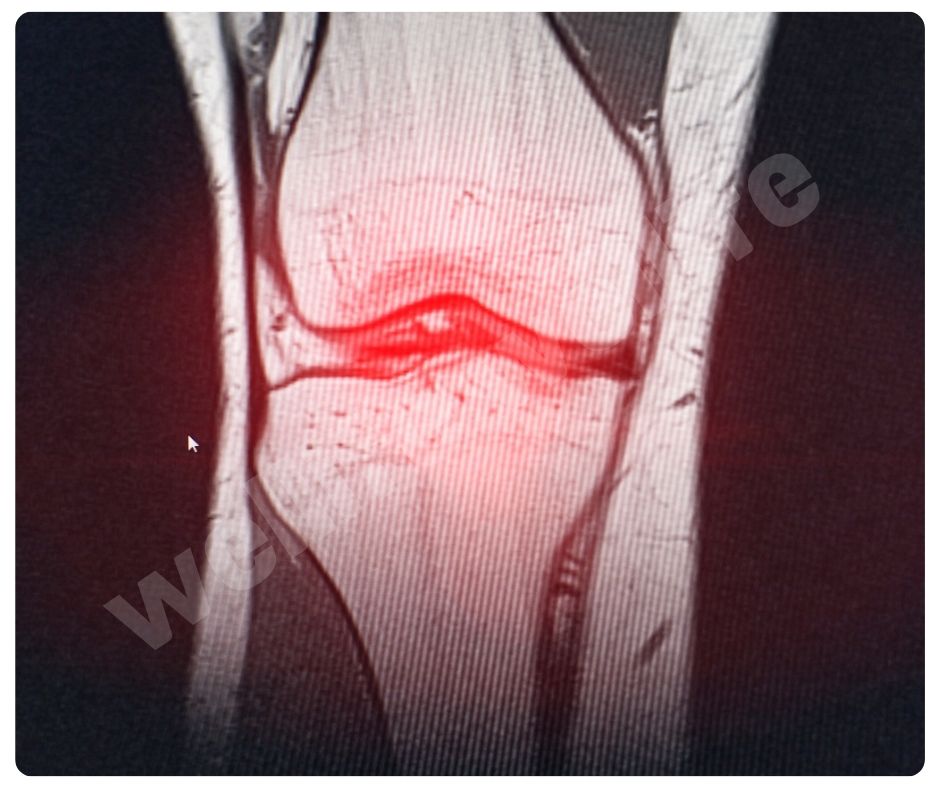

최근 연구에 따르면 콘드로이친 효능은 연골 세포의 생성을 촉진하고, 연골 조직의 회복을 돕는 효능이 있어요. 2023년에 발표된 한 연구에서는 콘드로이친이 연골 세포의 대사 활동을 증가시키고, 연골 조직의 손상을 줄이는 데 효과적이라는 결과를 보여주었습니다.

2022년에 발표된 연구에서는 콘드로이친이 관절 보호 효과를 강화하는 데도 중요한 역할을 한다는 결과가 나왔습니다. 이는 특히 무릎 관절에 좋은 영향을 미친다고 합니다 .